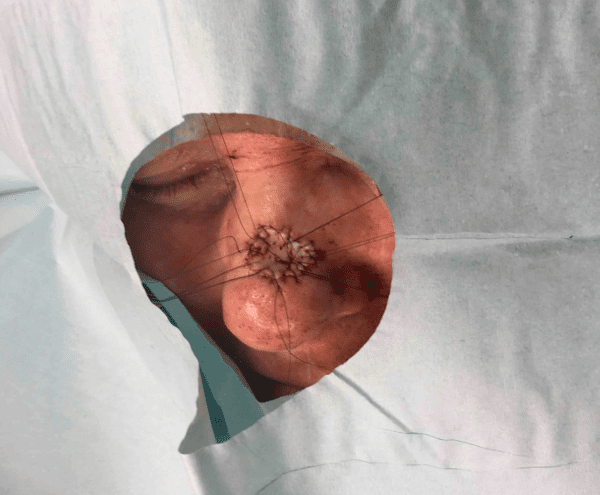

Male patient with history of longstanding rhinophyma to right and left alar rims of the nose. Patient underwent rhinophyma resection.